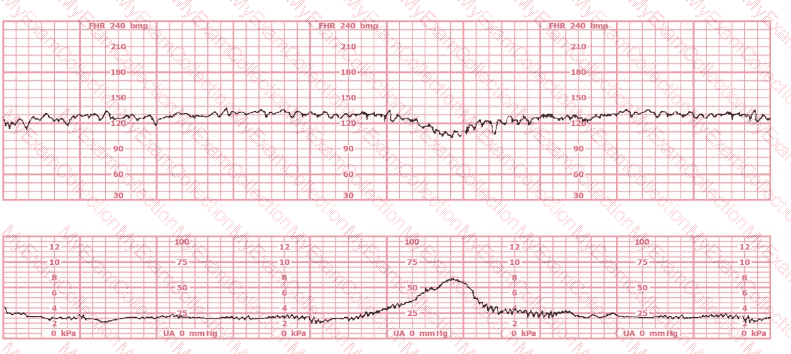

The most probable underlying fetal physiologic cause for this tracing would be:

A woman is being induced with oxytocin. The tracing shown is representative of 20 minutes. Based on this tracing, the next step would be to:

A 30-year-old woman (G2P0) is experiencing preterm labor at 26-weeks gestation. She is receiving magnesium sulfate for neuroprotection. Her external fetal monitoring tracing over the past 30 minutes is shown. The next step would be to:

A woman has been 5 cm dilated for the past 3 hours. The tracing shown has developed over the last 30 minutes. The best initial course of action is to: